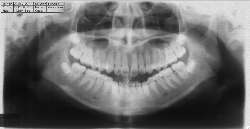

ステップ3. レントゲン (パノラマ,セファロ)撮影 口腔内写真撮影

口腔内写真,レントゲン

ステップ3. レントゲン(パノラマ、セファロ)撮影・口腔内写真撮影

ステップ5.精密検査

口腔内写真、レントゲン(必要に応じて CT )、印象(歯型)採得